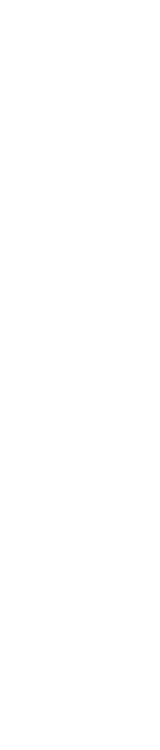

W płucach badanych w rzeźni najczęściej obserwowanymi zmianami są zapalenie oskrzeli i płuc w części dobrzuszno-doczaszkowej oraz zapalenie opłucnej.

Zapalenia płuc i oskrzeli w części dobrzuszno-doczaszkowej są głównie związana z enzootyczną bronchopneumonią. Mają one postać obszarów zagęszczenia, są twarde w dotyku i mają barwę od szarej do fioletowej, w zależności od wieku zmiany i wtórnych powikłań bakteryjnych.